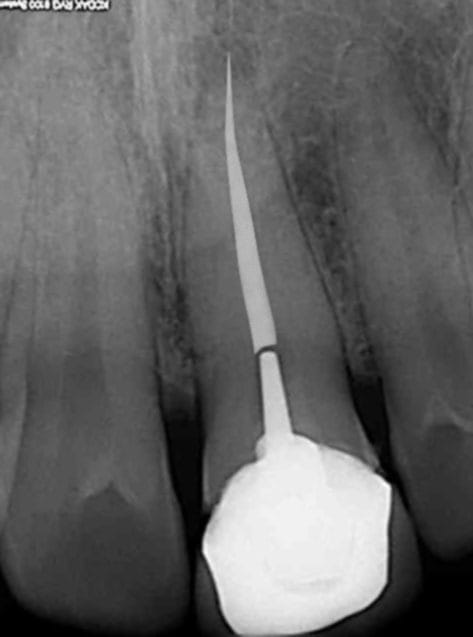

Pas mal photo shop. mais j'ai des progrès à faire. Superbe endo en tout cas vive la vague de gutta chaude. )))))))

R1 modifie  1 mextcw - Eugenol

Un peu trop blanc mais ça simplifie la sélection après. Une fois re sélectionné, il suffit de modifier la teinte pour un peu plus de grisé.

C'est un nouveau matériau d'obturation, hyper dense !))))je me suis servi de la gomme. C'est le bordel pour choisir les couleurs.

Celle là est mieux, Comment fait on pour changer les couleurs du crayon ?